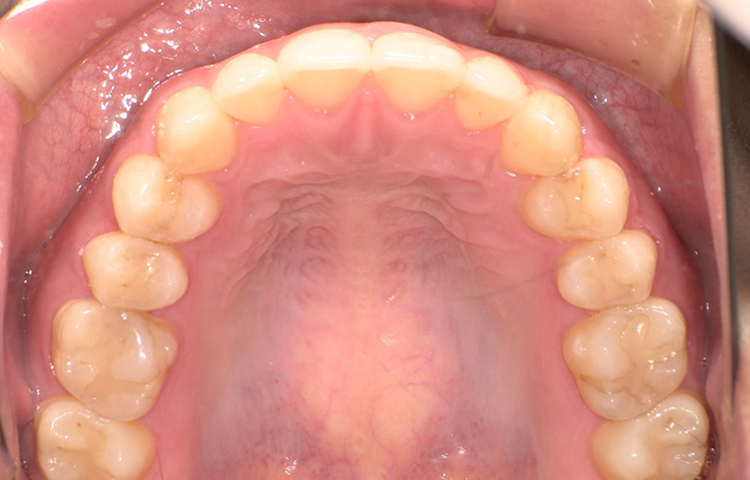

治療前

治療後

| 主訴 | 上の前歯のガタつきが気になるので前歯だけ綺麗にして欲しい |

|---|---|

| 治療 期間 |

約6ヶ月 |

| 治療費 | 165,000円(税込)/調整費用別途 |

| 治療 内容 |

上の前歯部にワイヤーを着けて進めていく、プチ矯正で施術。 |

| 治療の リスク |

見た目を綺麗にする目的で短期間で仕上げる為噛み合わせは矯正しない。 |